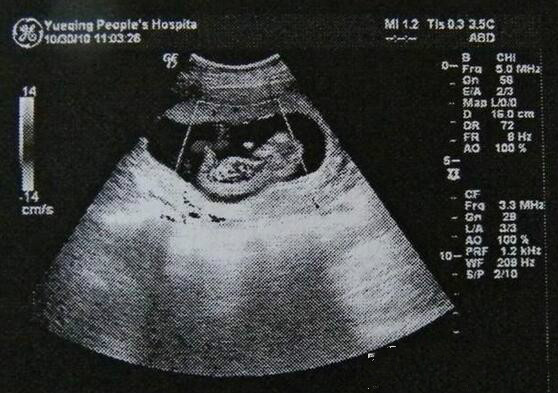

其实怀孕1个月的时候b超照片是看不出来胎儿长什么样子的,因为在这期间的胚芽,身体分两大部分,非常大的部分为头部,占了身长的一半,头部相连着的躯体,有长长的尾巴,很像小海马的形状。这时人类的胚芽,在外观上,与其他动物的胚芽没有什么区别,手脚因为太小,肉眼还看不清楚。这个时期的胎儿,眼睛、鼻子、耳朵尚未形成,但嘴和下巴的雏形已经能看到了。血液循环系统器官原型已出现,脑、脊髓神经系统器官原型也已出现,肝脏在这个时期也开始显著发育,心脏的发育较显著,在第2周末成形,从第3周末起开始搏动,与母体相连的胎盘,脐带也从这个时候开始发育了。胚芽的表面覆盖着绒毛组织,这种组织不久将要形成胎盘。胎儿通过胎盘吸收母体的营养成分,排出代谢产物。

除此之外很多女性担心在怀孕早期做B超检查会对胎儿造成影响,妇产科专家介绍怀孕一个月做b超对胎儿是没有影响的,b超检查可以确定孕囊发育是否正常等。孕期5次B超检查只是一般健康、正常的孕妇所需的检查次数,若遇到特殊的病理情况,如发现胎儿生长受限、胎儿宫内缺氧、胎儿畸形、羊水过多或过少等,医生还将根据临床实际情况另行增加医学需要的B超检查次数。选择合适的时机进行B超检查非常重要,因为有些疾病的筛查有严格的时间限制。结语:怀孕初期要学会摆脱压力,放松身心,期待宝宝的到来,良好的心态、积极的情绪,不但有助于提高受孕质量,对胎儿神经系统的发育也有很大的影响。